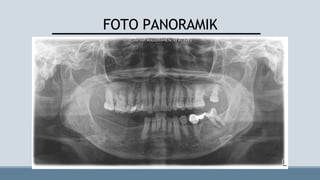

FOTO PANORAMIK

KAJIAN RADIOGRAFIK

• Gigi hilang 27, 44, 45, 46, 47

•Tampak gambaran radiopak kesan tumpatan pada gigi 14 dan 15

• Tampak gambaran radiopak kesan bahan pengisi saluran akar dan tumpatan pada

gigi 37

• Tampak gambaran radiopak kesan mahkota gigi tiruan pada gigi 35 dan 36

KAJIAN RADIOGRAFIK • Gigihilang 27, 44, 45, 46, 47 •Tampak gambaran radiopak kesan tumpatan pada gigi 14 dan 15 • Tampak gambaran radiopak kesan bahan pengisi saluran akar dan tumpatan pada gigi 37 • Tampak gambaran radiopak kesan mahkota gigi tiruan pada gigi 35 dan 36